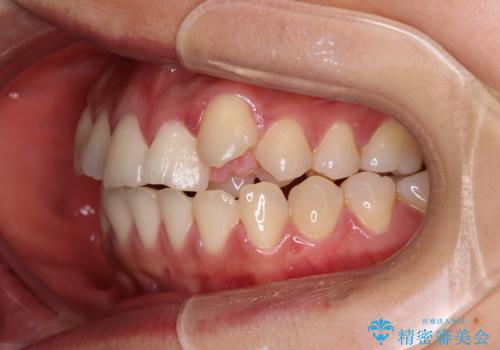

- 左上の前歯のがたつきを主訴に来院された患者様です。

上顎歯列が下顎の歯列に対して狭小であり、一部下顎の奥歯が上顎よりも外側に位置している状態でした。

上顎の歯列を拡大しスペースを設け、さらに左上の小臼歯を一本抜歯し左上の八重歯を歯列内に入れ整えていくことにしました。